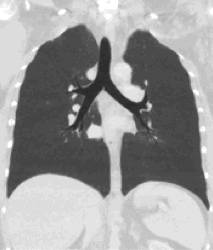

A CT scan can be used for detecting both acute and chronic changes in the lung parenchyma, the tissue of the lungs.[41] It is particularly helpful because normal two-dimensional X-rays do not show such defects. A variety of techniques are used, depending on the suspected abnormality. For evaluation of chronic interstitial processes such as emphysema, and fibrosis,[42] thin sections with high spatial frequency reconstructions are used; often scans are performed both on inspiration and expiration. This special technique is called high resolution CT that produces a sampling of the lung, and not continuous images.[43]

HRCT images of a normal thorax in axial, coronal and sagittal planes, respectively.